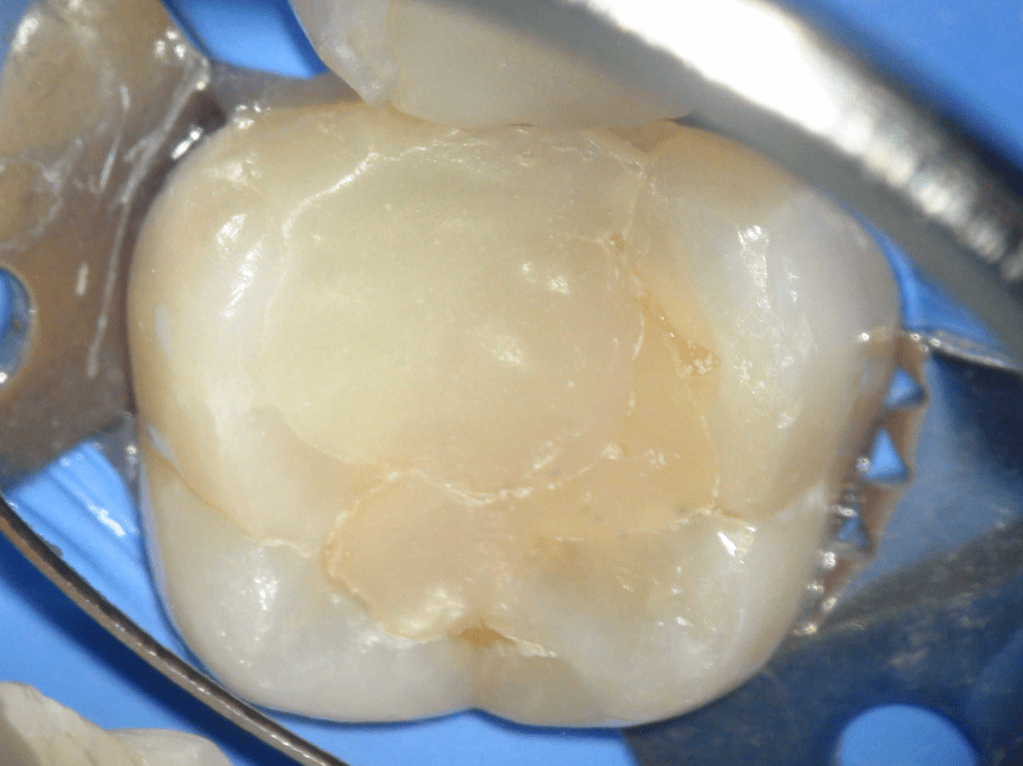

Acceso ultraconservador a través de incrustación reciente